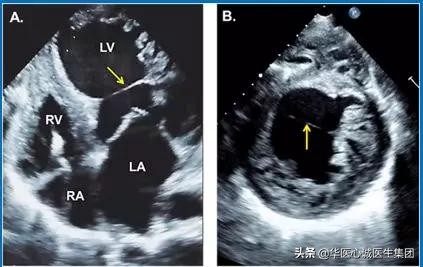

超声心动图

可表现为Q尾征,见箭头处。

牛角状的为患者的左心耳,上方为左上肺静脉。

二者间的隔膜为华法林嵴,类似棉签样改变。